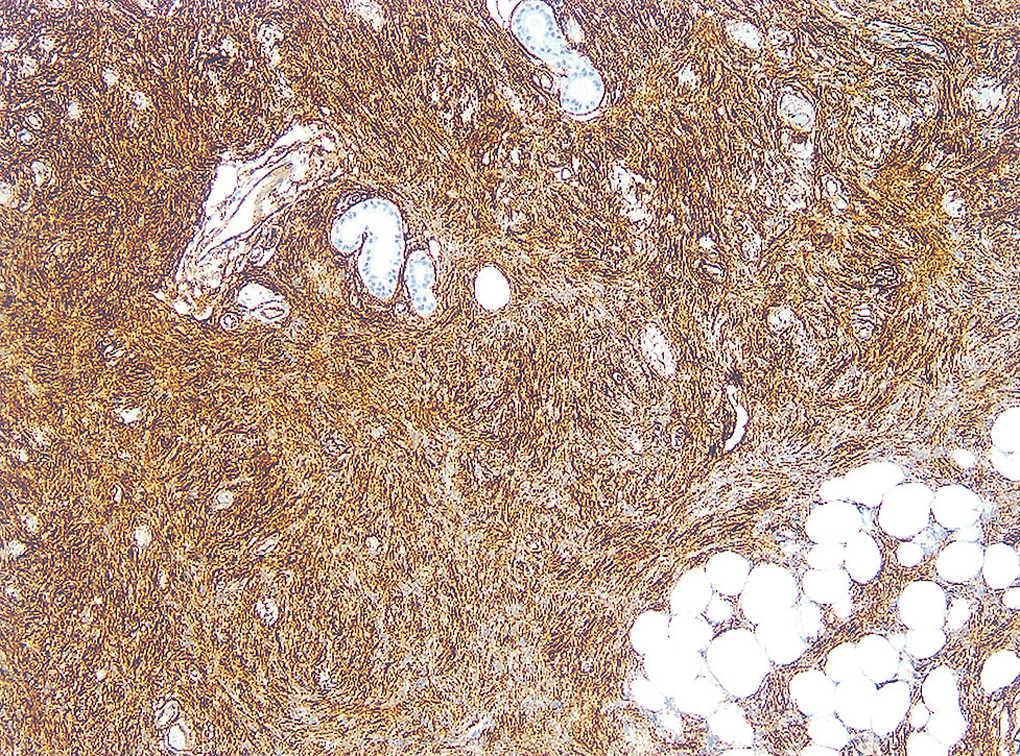

Fig. 2.--Haces de células fusiformes arremolinadas en patrón en rueda de carro.

Fig. 3.--Detalle de la figura 2.

El estudio histopatológico mostró en la dermis profunda una densa proliferación de células fusiformes con núcleos abombados, levemente pleomórficos. Éstas estaban dispuestas en haces entrelazados con un patrón arremolinado en torno a un eje central constituido fundamentalmente por colágeno y alcanzaban el tejido celular subcutáneo.

La apariencia histopatológica típica del DFSP consiste en una densa proliferación de células fusiformes con núcleo abombado, dispuestas en haces arremolinados en un patrón estoriforme denominado en rueda de carro, alrededor de áreas acelulares centrales de tejido colágeno 4. Desde esta zona parten radialmente fascículos de células neoplásicas que invaden el tejido adiposo subcutáneo desde la dermis profunda, ya sea dejando islotes de adipocitos entre los fragmentos del tumor (patrón en panal de abejas, 30 % de los casos), ya sea en bandas paralelas a la epidermis (patrón en hojaldre, 60 % de los casos). Las células muestran grandes núcleos ligeramente pleomórficos, con escasas figuras mitóticas. En su periferia, el tumor tiende a crecer emitiendo prolongaciones mal delimitadas, lo que explica la dificultad clínica e histológica para determinar sus límites y la elevada tasa de recurrencia tras la extirpación quirúrgica convencional 8. El DFSP muestra positividad para CD34 y negatividad para factor XIIIa y proteína S-100, de gran valor para el diagnóstico diferencial con otros tumores.